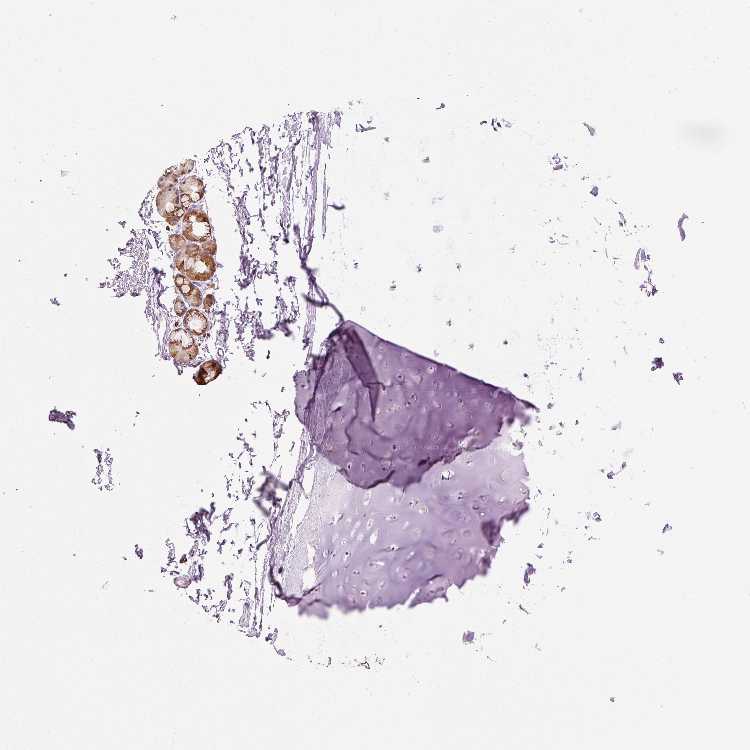

SOFT TISSUE 1 - Antibody stainingi

Antibody staining in the annotated cell types in the current human tissue is reported as not detected, low, medium, or high, based on conventional immunohistochemistry profiling in selected tissues. This score is based on the combination of the staining intensity and fraction of stained cells.

Each image is clickable and will lead to virtual microscopy that enables deeper exploration of all samples and also displays staining intensity scores, fraction scores and subcellular localization as well as patient and tissue information for each sample.

Antibody HPA055141

Chondrocytes Not detected

Fibroblasts Not detected

Peripheral nerve Not detected

SOFT TISSUE 2 - Antibody stainingi